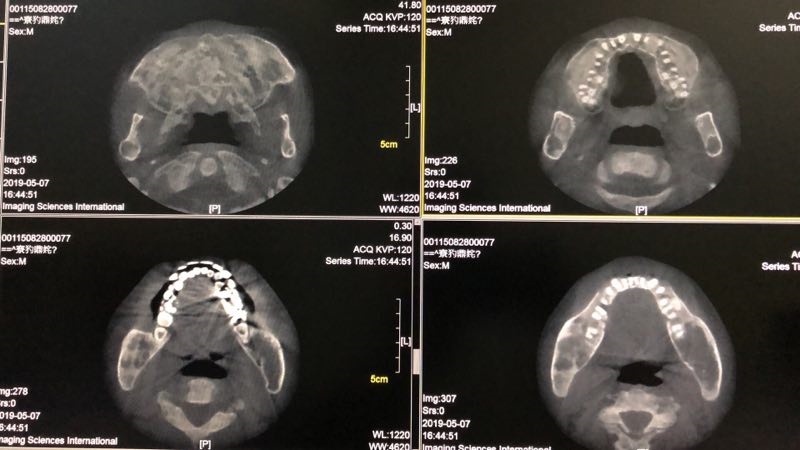

辅助检查:糖化血红蛋白6.2%;甲状旁腺激素87pg/ml(15-65);25-羟维生素D23.63ng/ml(>20) ;血镁0.71mmol/L(0.66-1.07);血钙2.32mmol/L(2.15-2.55) ;血磷0.83mmol/L(0.81-1.45);24小时尿钙3.01nmol/24h(2.5-7.5);24小时尿磷10.9nmol/24h(13-42);TP1NP:1052ng/ml(9.06-72.64);β-CTX :2.68ng/ml(0.043-0.783);骨钙素:255.3ng/ml(24-70);血碱性磷酸酶:691U/L(40-129);血清抗酒石酸酸性磷酸酶:10.3U/L(≤4.47);骨源性碱性磷酸酶:75U/L;人护骨素:110ng/L ;骨密度(DXA):左前臂骨密,Z值-6.9;腰椎骨密度正常;胸腰段正侧位片示:考虑骨纤维异常增殖症伴骨质疏松;颌骨CT示:上颌骨地图样改变,下颌骨囊状空泡、丝瓜瓢状改变,考虑骨纤维异常增殖症;右上肢平片示:囊状膨胀性、丝瓜瓢状改变;胸片:考虑骨纤维异常增殖症。

▼ 颌骨CT示: